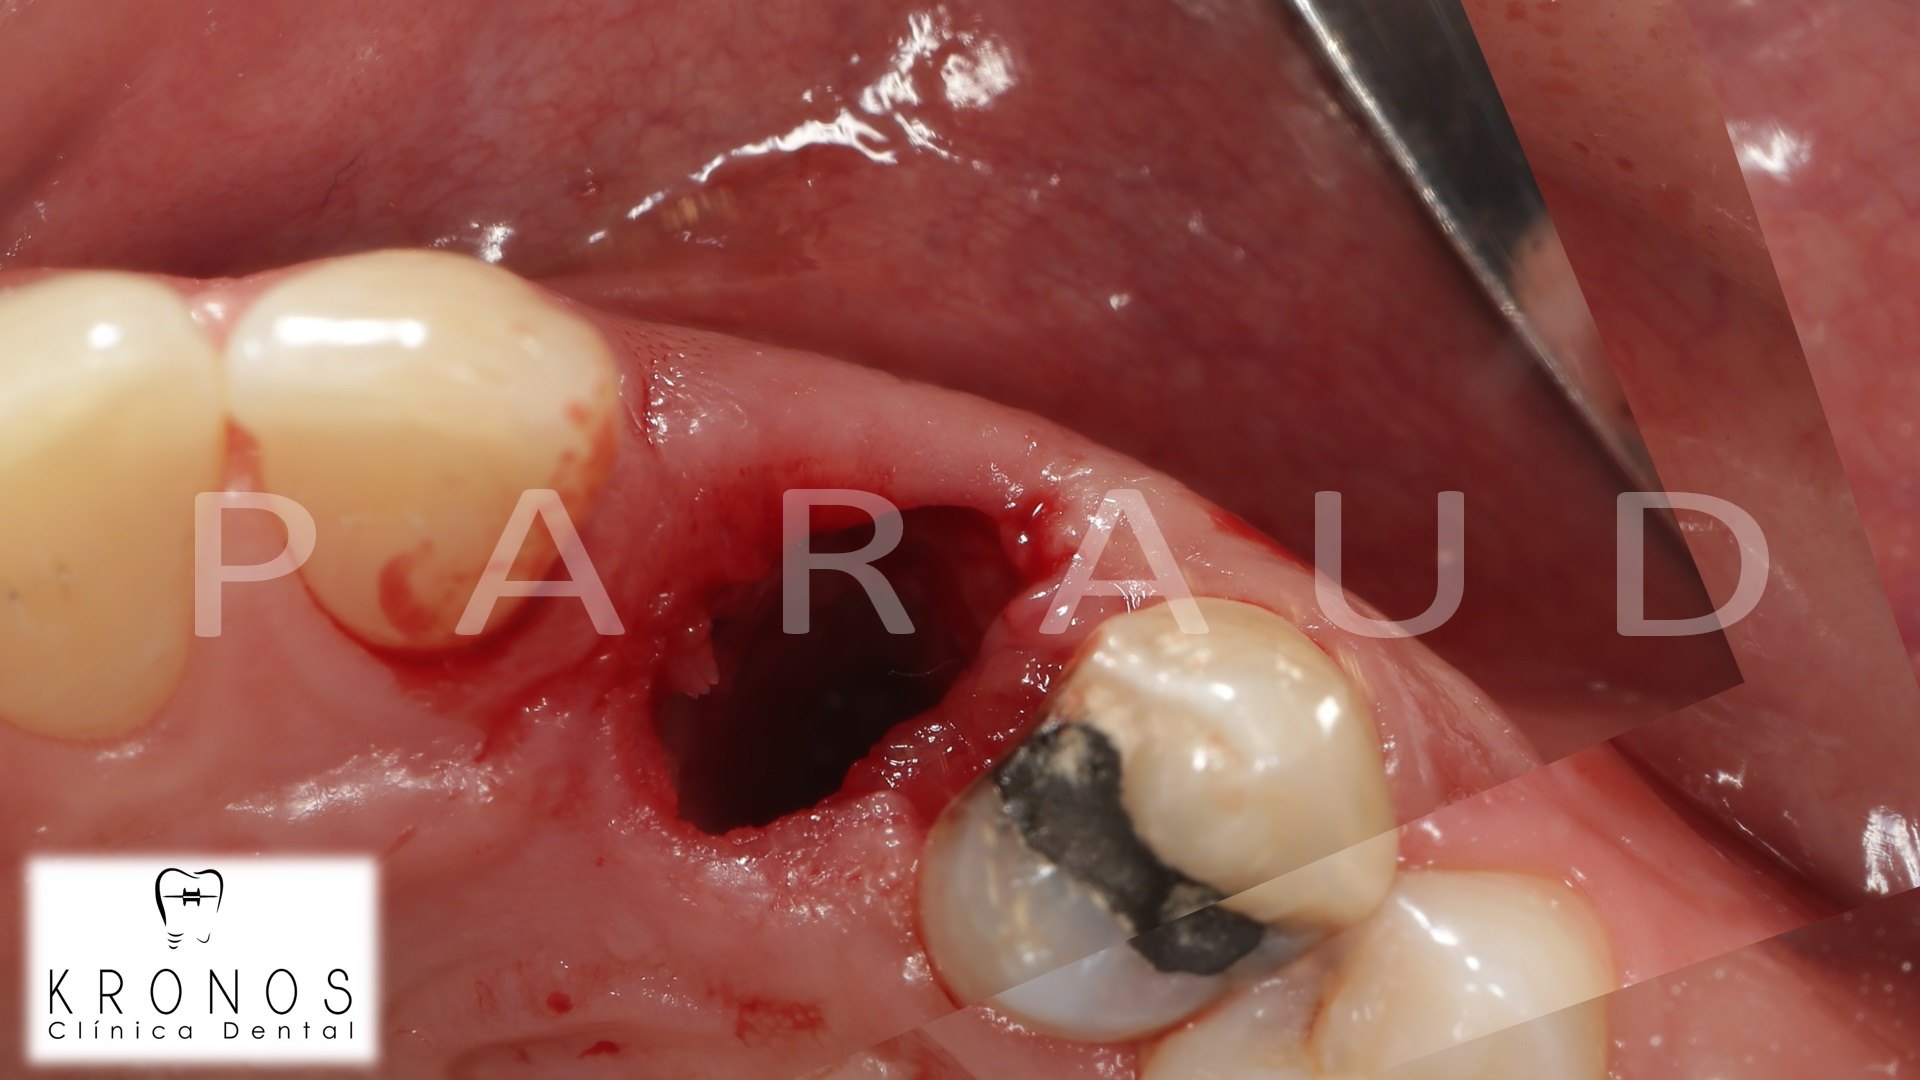

Clinical case: AnyRidge immediate loading

- Courtesy of Dr. Andres Paraud Freixas, Chile -

AnyRidge, ISQ value, initial stability, immediate loading, KnifeThread, maxillary anterior, Mega ISQ, Dr. Andres Paraud Freixas

AnyRidge implant system, Mega ISQ, Digital prosthesis